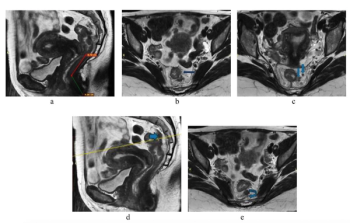

In a recent interview, Wayne Brisbane, M.D., discussed new research, presented at the American Urological Association (AUA) conference, which revealed a 15 percent higher AUC for an emerging AI software in detecting seminal vesicle invasion (SVI) in comparison to prostate MRI alone.